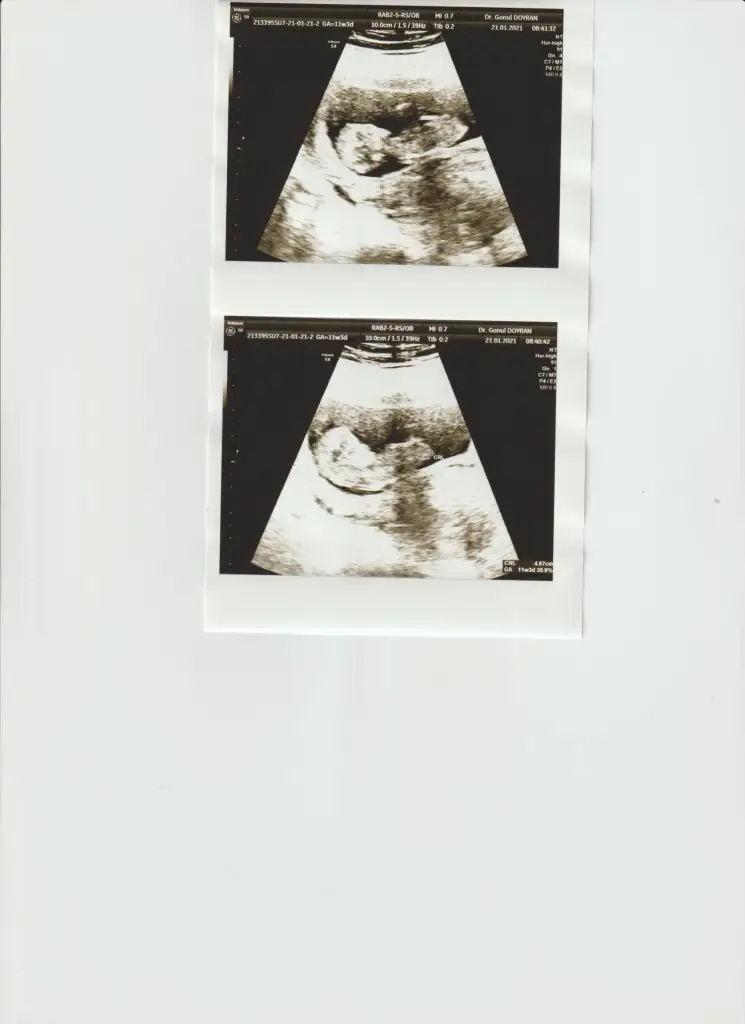

Bana da yorum yapabilirsiniz 12+4

Eklentiler

• IMG_20210125_140510.webp

IMG_20210125_140510.webp

20,3 KB · Görüntüleme: 84